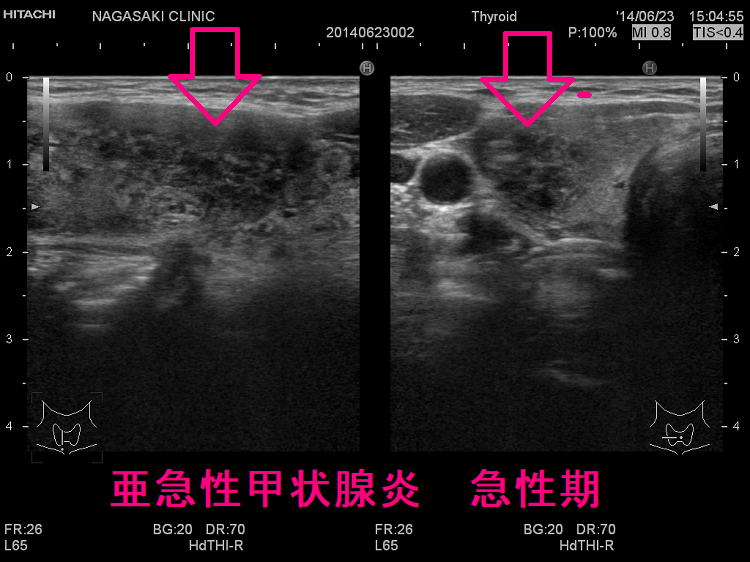

長崎甲状腺クリニック(大阪)オリジナルの亜急性甲状腺炎の治療は、中途再燃・再発を防ぐため、超音波(エコー)検査で炎症範囲を毎回調べ、改善度に応じてステロイド量を調整。炎症の強い部分は黒く、血流乏しく、エラストグラフィーで青くなる。副作用チェックはステロイド肝障害・膵炎・筋障害・低カリウム血症・糖尿病。甲状腺乳頭癌の合併、亜急性甲状腺炎ではなく、甲状腺乳頭癌の事も。亜急性甲状腺炎はバセドウ病,橋本病に合併、あるいは誘発する事も。頚部腫大、甲状腺中毒症が先行する場合、エコー検査で偶然見つかる事も。数年かかっても完全治癒しない亜急性甲状腺炎も稀に存在。

下は亜急性甲状腺炎の超音波(エコー)画像で、炎症の強い部分は黒く、エラストグラフィーでは青くなります。